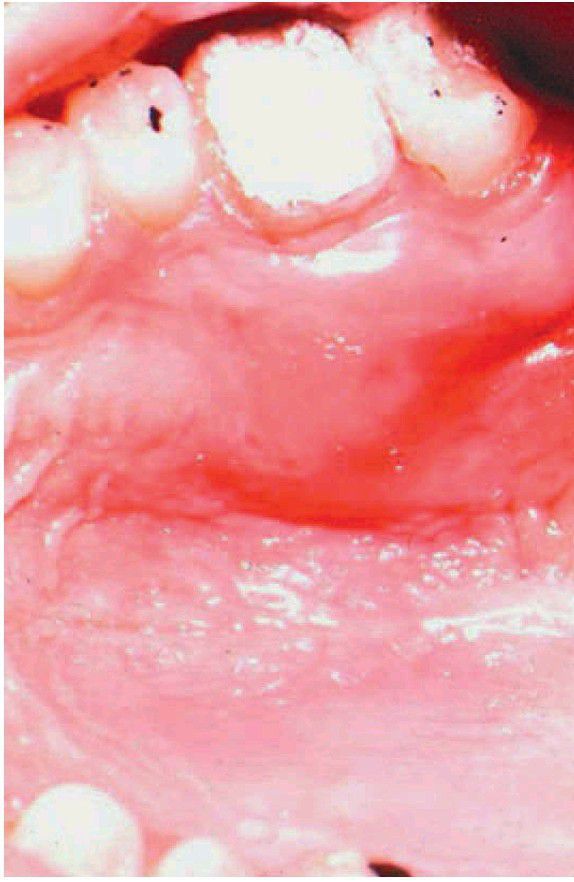

Palatal space infection

Fluctuant swelling in the posterior palate associated with periradicular disease from the lingual root of the maxillary first molar.